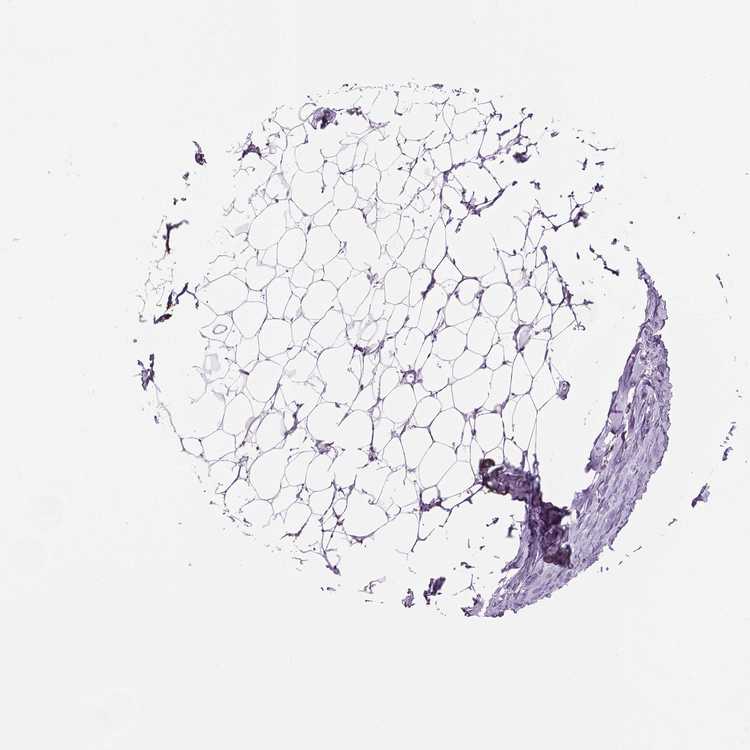

BREAST - Antibody stainingi

Antibody staining in the annotated cell types in the current human tissue is reported as not detected, low, medium, or high, based on conventional immunohistochemistry profiling in selected tissues. This score is based on the combination of the staining intensity and fraction of stained cells.

Each image is clickable and will lead to virtual microscopy that enables deeper exploration of all samples and also displays staining intensity scores, fraction scores and subcellular localization as well as patient and tissue information for each sample.

Antibody HPA045703

Adipocytes Not detected

Glandular cells Not detected

Myoepithelial cells Not detected